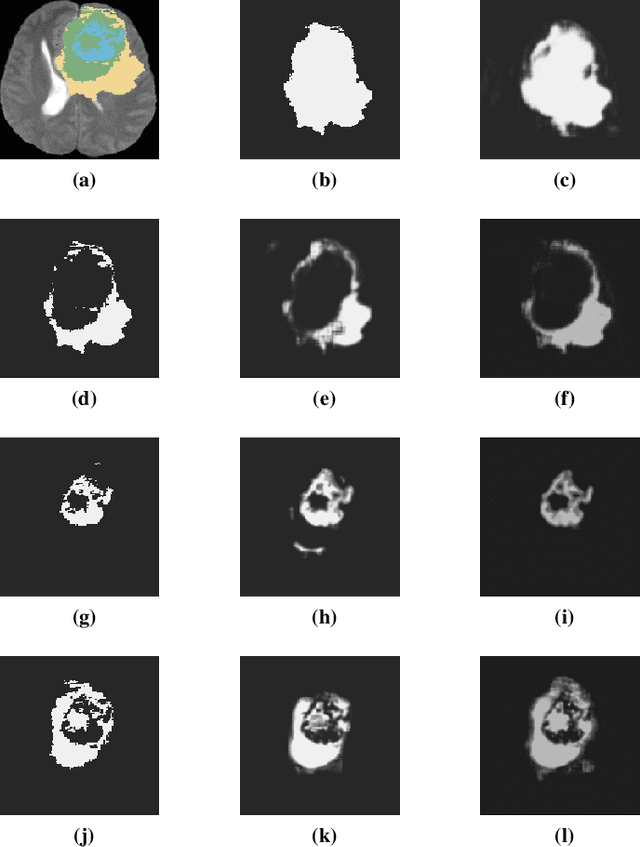

Abstract:Glioblastoma Multiforme is a very aggressive type of brain tumor. Due to spatial and temporal intra-tissue inhomogeneity, location and the extent of the cancer tissue, it is difficult to detect and dissect the tumor regions. In this paper, we propose survival prognosis models using four regressors operating on handcrafted image-based and radiomics features. We hypothesize that the radiomics shape features have the highest correlation with survival prediction. The proposed approaches were assessed on the Brain Tumor Segmentation (BraTS-2020) challenge dataset. The highest accuracy of image features with random forest regressor approach was 51.5\% for the training and 51.7\% for the validation dataset. The gradient boosting regressor with shape features gave an accuracy of 91.5\% and 62.1\% on training and validation datasets respectively. It is better than the BraTS 2020 survival prediction challenge winners on the training and validation datasets. Our work shows that handcrafted features exhibit a strong correlation with survival prediction. The consensus based regressor with gradient boosting and radiomics shape features is the best combination for survival prediction.

Abstract:Glioma, the malignant brain tumor, requires immediate treatment to improve the survival of patients. Gliomas heterogeneous nature makes the segmentation difficult, especially for sub-regions like necrosis, enhancing tumor, non-enhancing tumor, and Edema. Deep neural networks like full convolution neural networks and ensemble of fully convolution neural networks are successful for Glioma segmentation. The paper demonstrates the use of a 3D fully convolution neural network with a three layer encoder decoder approach for layer arrangement. The encoder blocks include the dense modules, and decoder blocks include convolution modules. The input to the network is 3D patches. The loss function combines dice loss and focal loss functions. The validation set dice score of the network is 0.74, 0.88, and 0.73 for enhancing tumor, whole tumor, and tumor core, respectively. The Random Forest Regressor uses shape, volumetric, and age features extracted from ground truth for overall survival prediction. The regressor achieves an accuracy of 44.8% on the validation set.

Abstract:The paper demonstrates the use of the fully convolutional neural network for glioma segmentation on the BraTS 2019 dataset. Three-layers deep encoder-decoder architecture is used along with dense connection at encoder part to propagate the information from coarse layer to deep layers. This architecture is used to train three tumor sub-components separately. Subcomponent training weights are initialized with whole tumor weights to get the localization of the tumor within the brain. At the end, three segmentation results were merged to get the entire tumor segmentation. Dice Similarity of training dataset with focal loss implementation for whole tumor, tumor core and enhancing tumor is 0.92, 0.90 and 0.79 respectively. Radiomic features along with segmentation results and age are used to predict the overall survival of patients using random forest regressor to classify survival of patients in long, medium and short survival classes. 55.4% of classification accuracy is reported for training dataset with the scans whose resection status is gross-total resection.